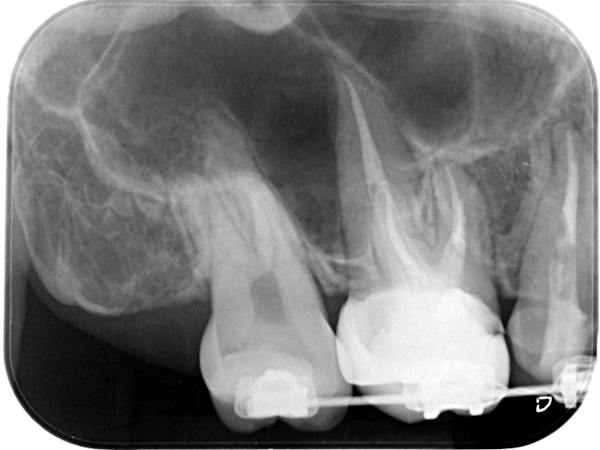

根管治療終了後3か月経過